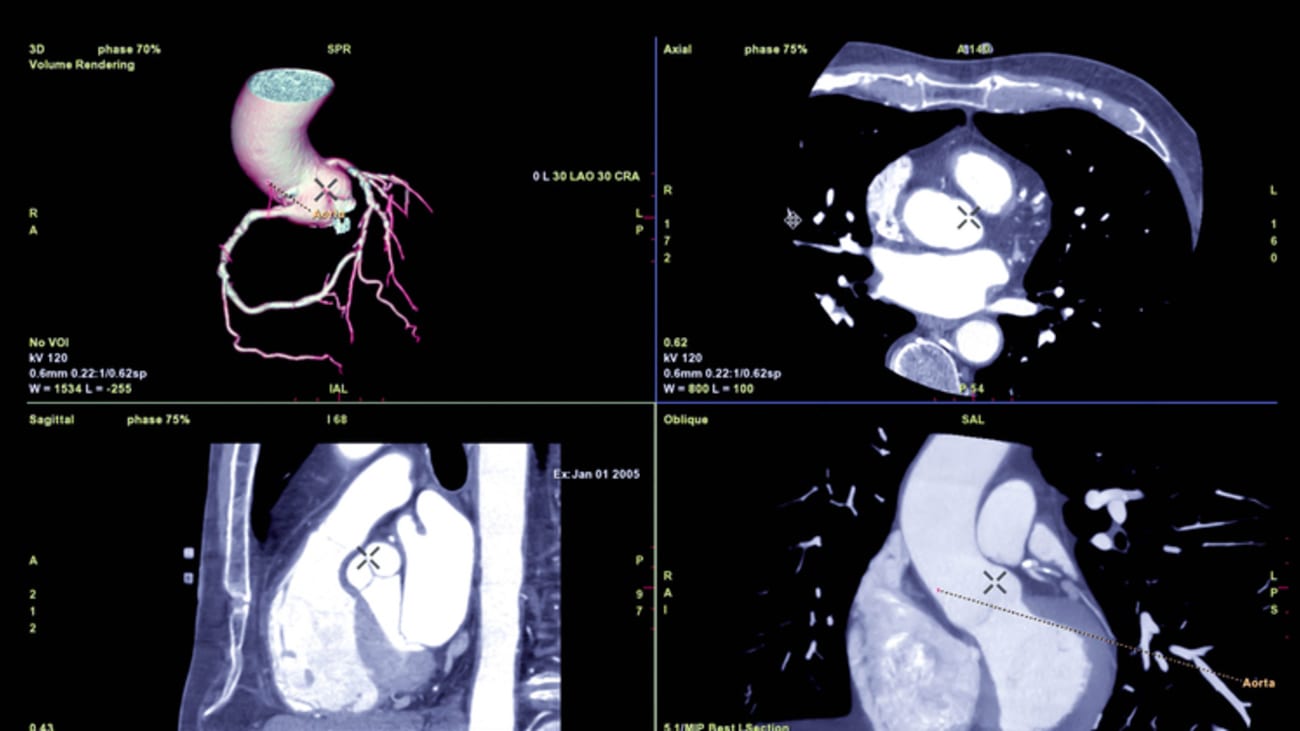

To understand the leap forward, it helps to look at how heart imaging has traditionally worked. A standard heart CT (computed tomography) scan provides doctors with a visual estimate of how narrowed an artery might be. It looks for "stenosis," or blockages, that impede blood flow.

Dr. Cury explains that the new AI-enabled scans go much further than simply identifying blockages.

"A traditional heart CT scan looks mainly for narrowings in the heart arteries and gives doctors a visual estimate of blockage severity," Dr. Cury said. "The AI-enabled heart CT goes several steps further."

This advanced software analyzes the CT images to quantify the disease itself, not just the space remaining in the pipe. "Instead of just asking — 'Is there a blockage?' — this technology helps answer 'How healthy are your arteries today and what risk do they pose in the future?' " Dr. Cury notes.